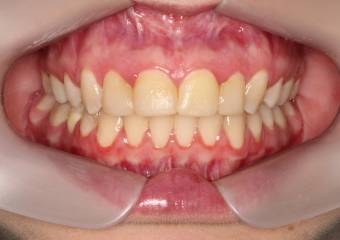

Oclusão após a cirurgia 2019